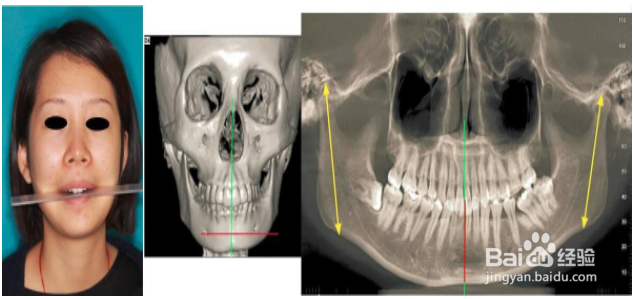

1、你自己对着镜子照下,看下自己牙齿咬合尺子 是否面部2测水平型,表现为颏部偏斜,无明显垂直向不对称,对侧前牙区反合或对侧磨牙舌倾。